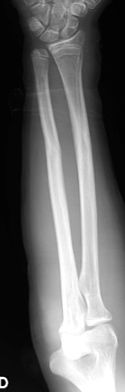

Las fracturas de ambos huesos del antebrazo al mismo nivel, con líneas de fractura oblicua-transversa o desplazamiento convergente son inestables y precisarán de tratamiento quirúrgico. En estos casos está indicado, dependiendo de la edad del paciente, el tratamiento mediante reducción y osteosíntesis. El enclavado intramedular elástico es el tratamiento de elección (Figura 15).

Figura 15: a-Imagen clínica de fractura de antebrazo derecho con gran deformidad. b- Radiografía donde se aprecia fractura de radio-cúbito de trazo transverso en el mismo nivel. c, d-Enclavado intramedular elástico. e,f- Imagen final con buena consolidación ósea.